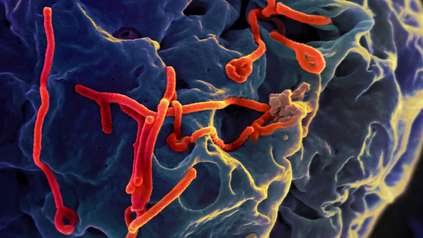

At the Wellcome Genome Campus we undertake genome and biodata research. We provide bioinformatics services to the world and we deliver vital training in genomics and biodata to scientists and clinicians. We are at the interface of research and industry translating science into tangible societal benefits.

At the Wellcome Genome Campus we undertake both wet and dry lab science, basic research and the delivery of bioinformatics resources for the global scientific community.